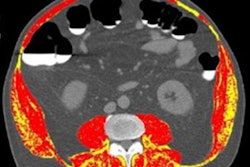

They first retrospectively gathered data from 133 patients, including 53 with normal bone mineral density, 32 with osteopenia, and 48 with osteoporosis. The SenseCare advanced visualization research platform (SenseTime) was used to automatically segment the L1-L4 vertebrae on the CT images. The researchers then extracted 1,197 radiomic features from these regions of interest using the open-source PyRadiomics software.